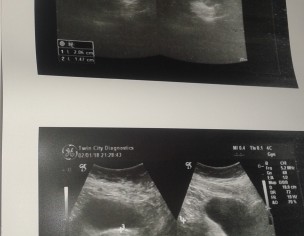

my mom is suffering from tumor in uterus. doctor has suggested her to take medicines there is no need of surgery. could any specialist could comment on that? ultrasound reports and dr's .prescription are attached

These are fibroids ( benign Tumours ) and the size they r at I really don’t think they need to be removed.. can u plz share if she’s having any symptoms? And plz don’t use danazol.. the drug has more side effects than uses

Uterine Fibroids cannot be treated with medicine, if she has symptoms it has to be surgically removed.